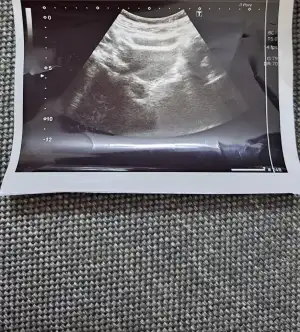

Kizlar bu ay klomen ile yumurta takibi yapildi. Pcos degilim ama yinede kullanmam gerekiyormus. Ilaca adetin 2.gunu basladim  cuma gunu bitti pazarteside kontrole gittim adetin 8.gunuydu. Üc yumurtan olusmus dedi. 12 14 mm dedi. Carsamba bida gel dedi. Bugun gittim 10.gunum bugun de 12 14 19 mm dedi 19 mm olan yumurta sagliksizmis aciklama yapmadi sagliksiz yumurta ne demek oluyor kistlesmemi var acaba  diger ikisi saglikli gorunuyor dedi. Benim anlamadigim iki gun oncede 12 14 mm den soz ediliyordu. Bugun yine 12 14 mm dedi cuma gunu tekrar gel dedi. Cok endiseliyim acaba o iki yumurtam gelismiyor olabilir mi? Iki gunun ultrason fotograflarini atacagim anlayip yardimci olabilecek biri varsa cok sevinirim mm olarak ben mi yanlis anladim acaba